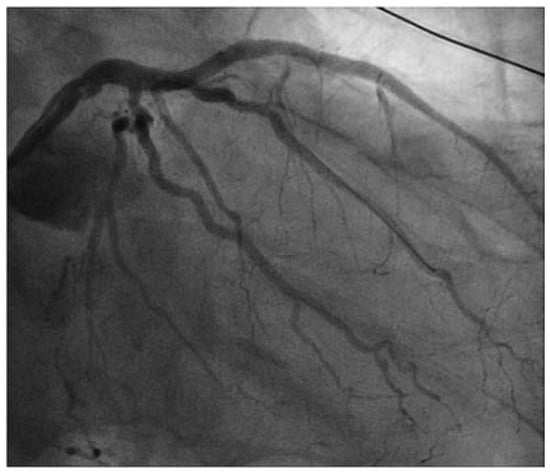

Case report A 22-year-old male experienced a presyncopal spell while studying for a university examination [...]